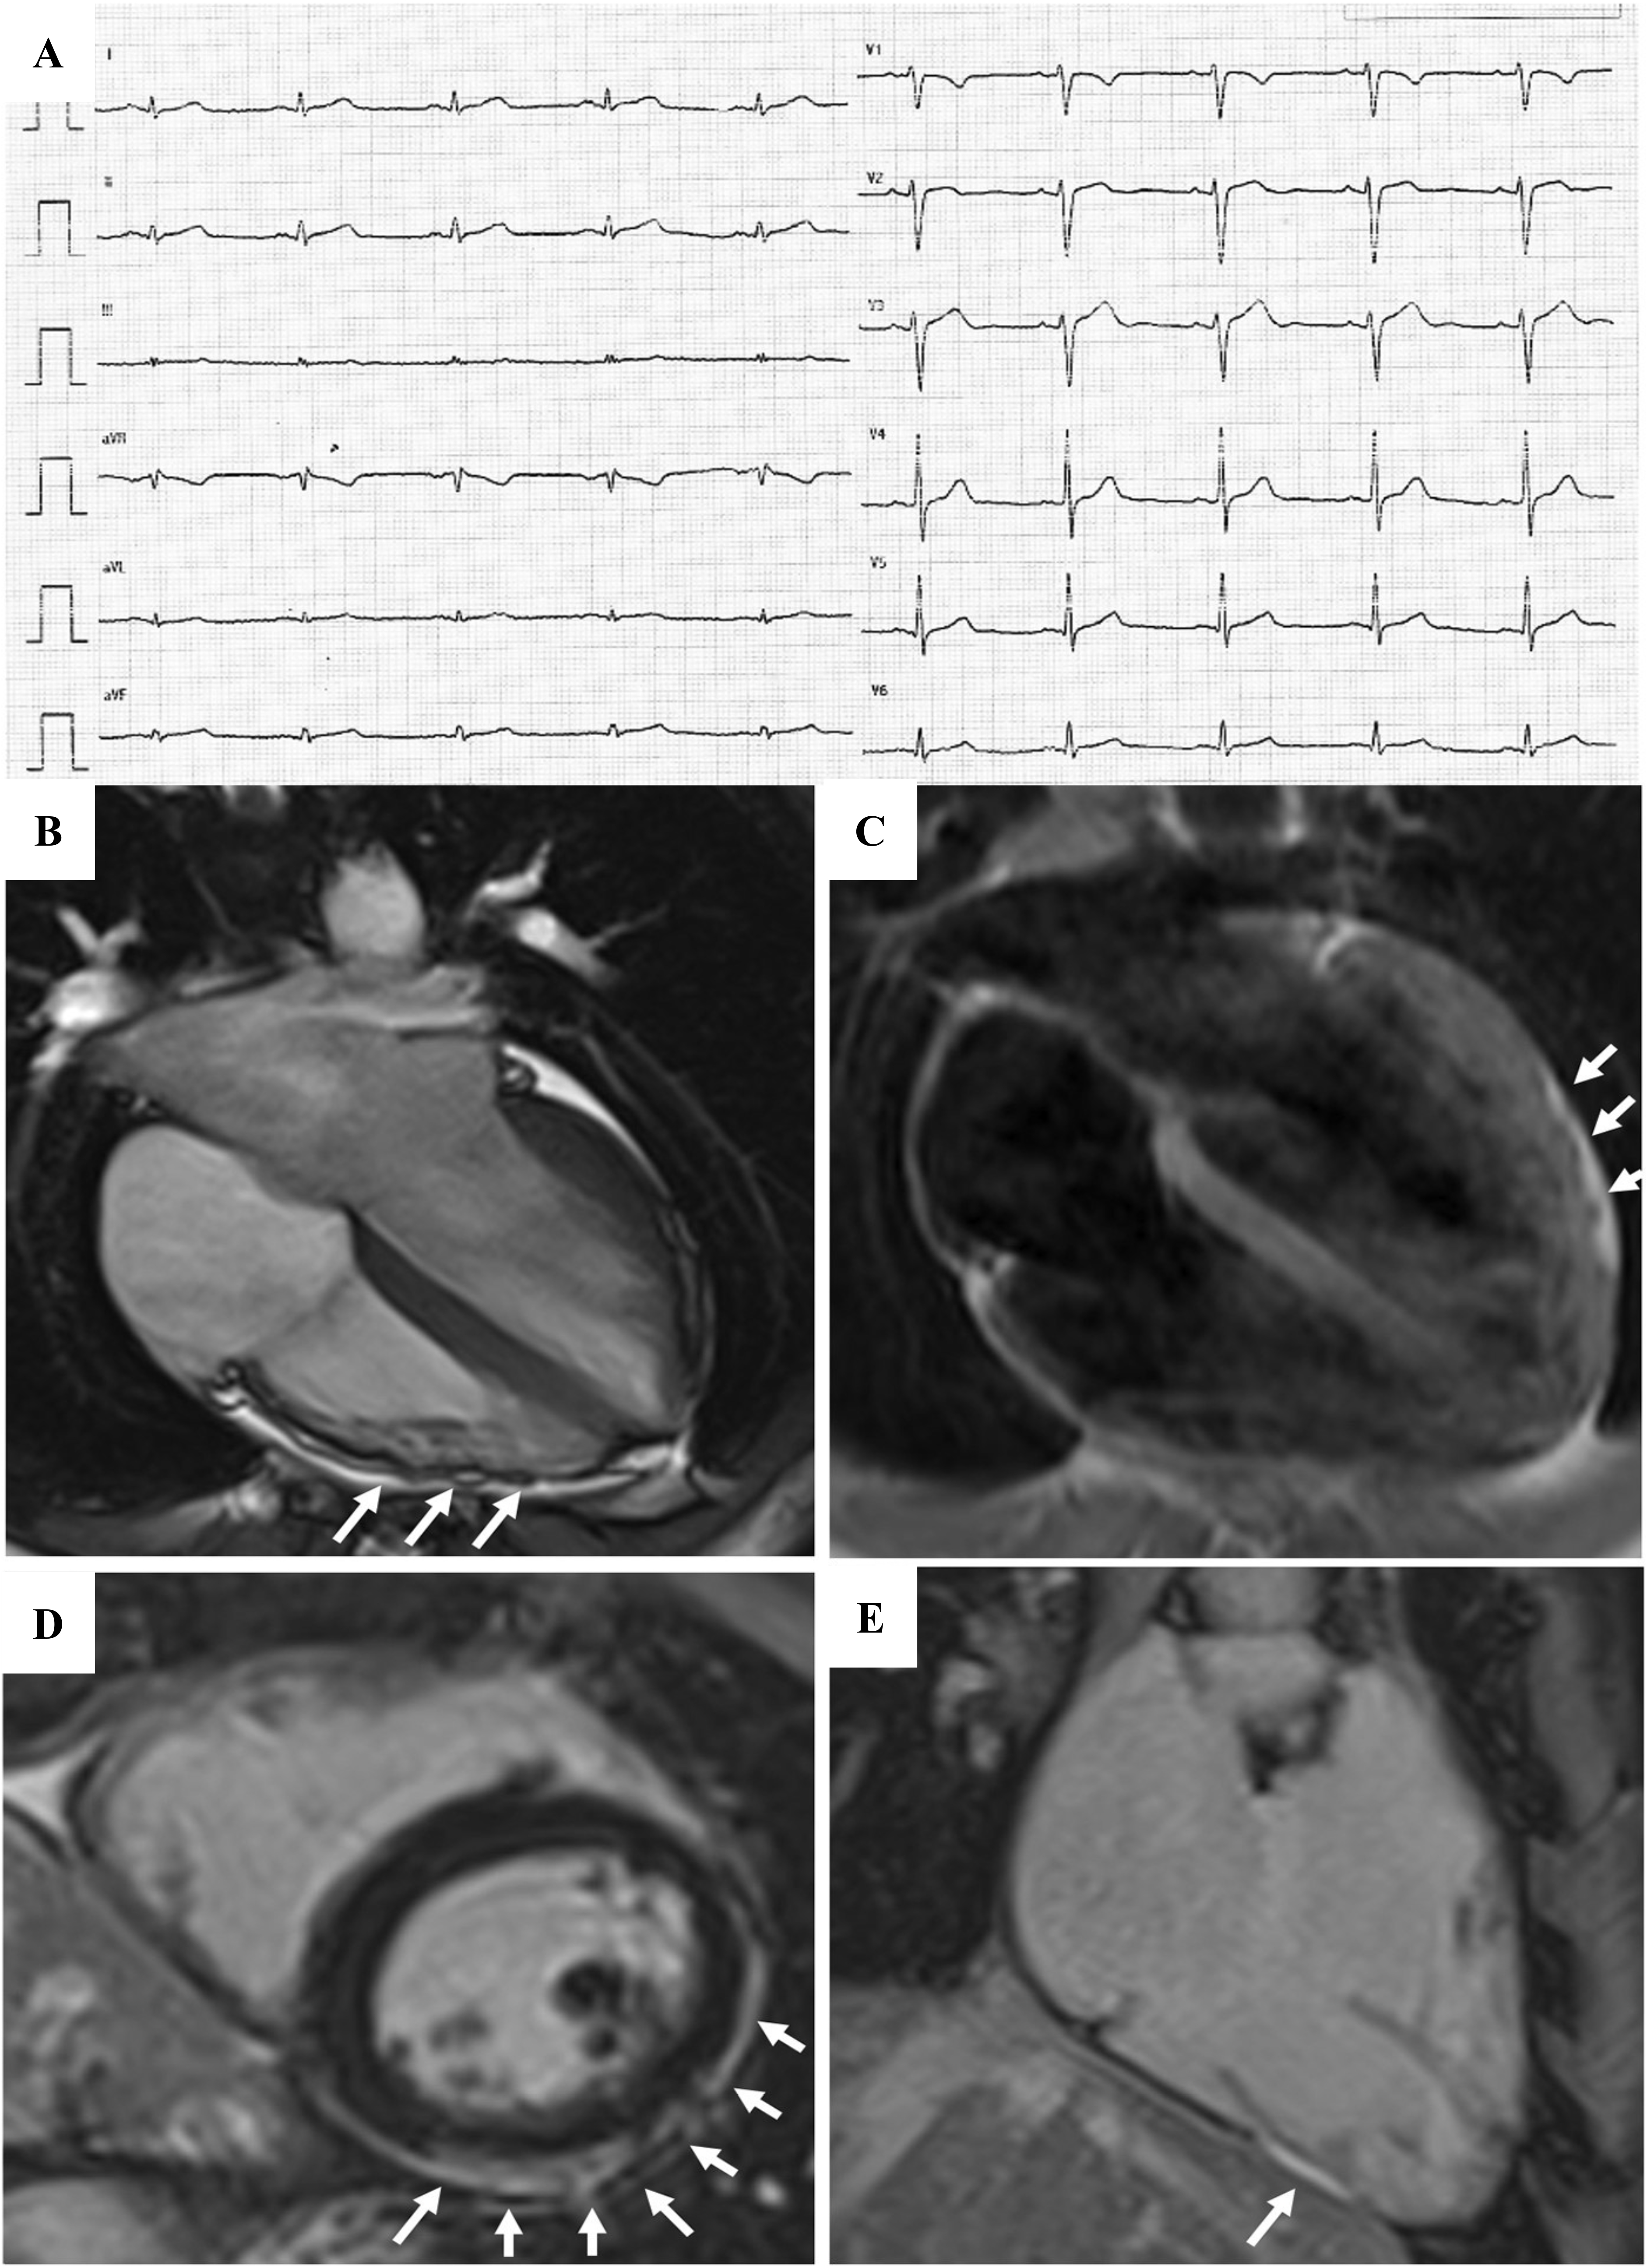

The presence of low QRS voltages in limb leads (peak-to-peak QRS amplitude

Fig. 5.Clinical features of biventricular ACM. Basal ECG and CMR findings in a 28-year-old elite athlete. ECG revealed low QRS voltages in limb leads (A). Exercise testing demonstrated PVBs with a RBBB/superior axis morphology, isolated and in couples. CMR cine-sequences showed hypokinesis of the mid-apical lateral wall and multiple small bulging of the RV free wall (B, four-chamber view). The PD-TSE sequences revealed epicardial fatty infiltration of the lateral and inferior LV walls (C, four-chamber view). Post-contrast sequences on CMR demonstrated a subepicardial stria of LGE involving the antero-lateral, infero-lateral and inferior LV walls (D, short- axis view) and also the RV inferior wall (E, RV inflow-outflow view). The diagnosis was “definite biventricular ACM”. ACM, arrhythmogenic cardiomyopathy; CMR, cardiac magnetic resonance; LV, left ventricle; PVBs, premature ventricular beats; PD-TSE, proton density-turbo spin echo; RBBB, right bundle branch block; RV, right ventricle. Adapted from Zorzi et al. [38].